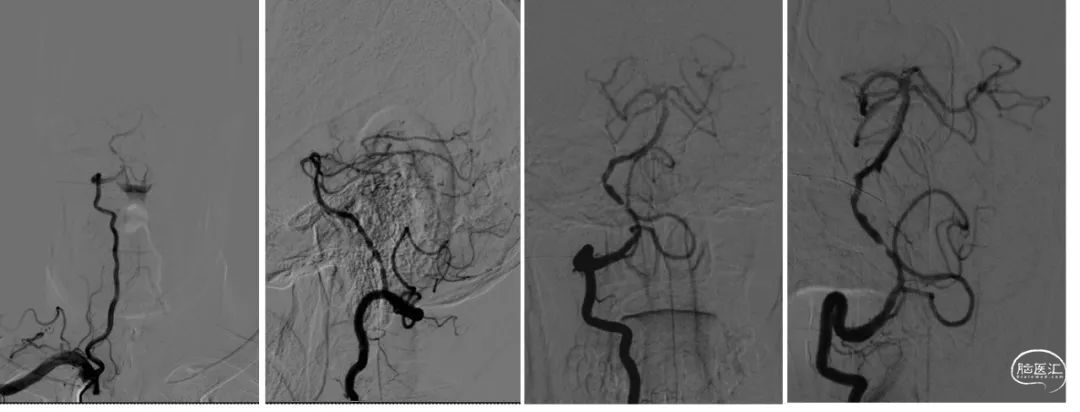

术前影像学检查

脑血管造影:主动脉弓+右侧颈总动脉造影。

左侧颈总动脉造影。

左侧锁骨下动脉造影。

右侧锁骨下动脉造影。

300cm微导丝携Gateway球囊到位,行球囊扩张及预扩张后造影。